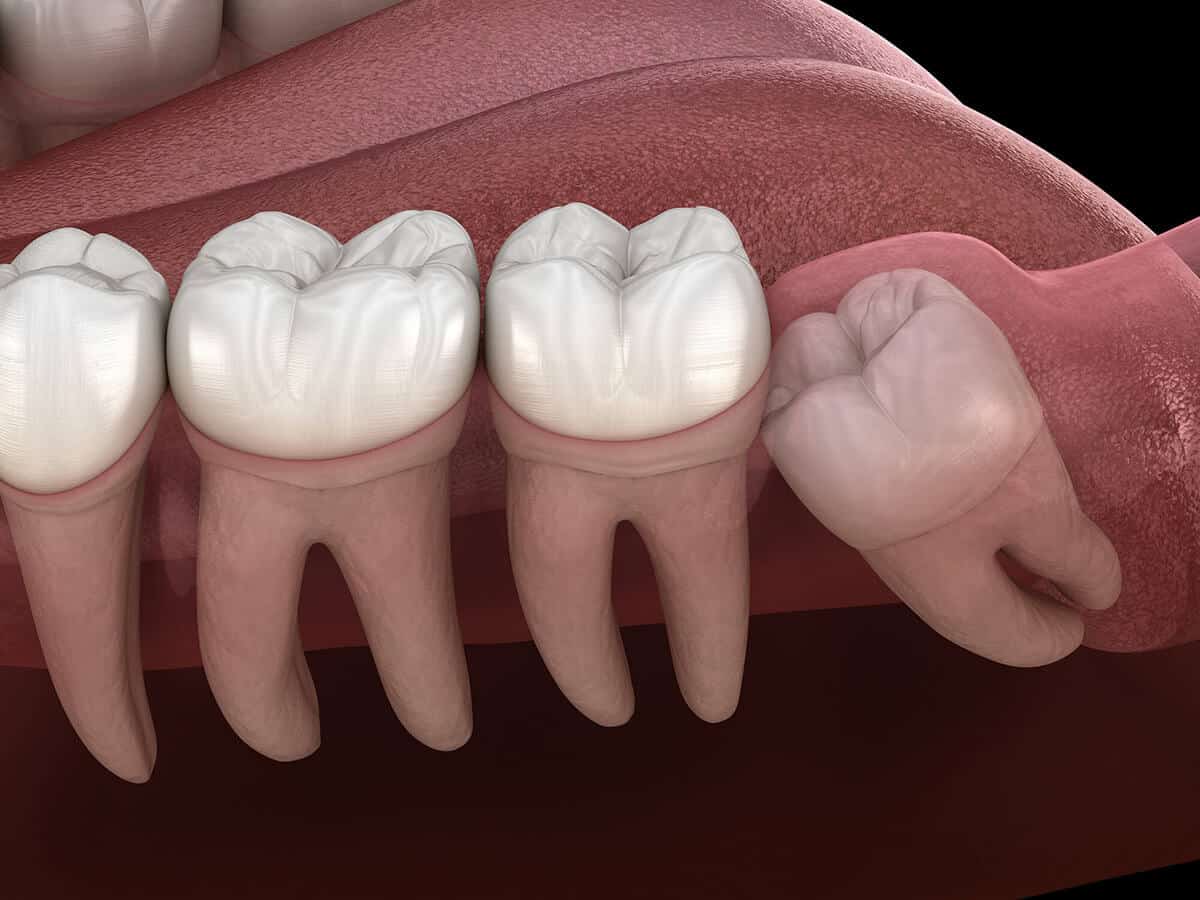

Wisdom teeth, also known as third molars, are the last set of teeth to emerge in the back of the mouth, typically between the ages of 17 and 25. While some people have enough space in their jaws to accommodate wisdom teeth without any issues, others may experience problems due to limited space, leading to the need for their removal.

There are several common reasons why wisdom teeth removal is recommended. These include impacted wisdom teeth (when the teeth do not fully erupt), overcrowding, misalignment, and the risk of potential complications such as infection, decay, and gum disease. Your dentist or oral surgeon will assess your situation and recommend extraction if necessary.